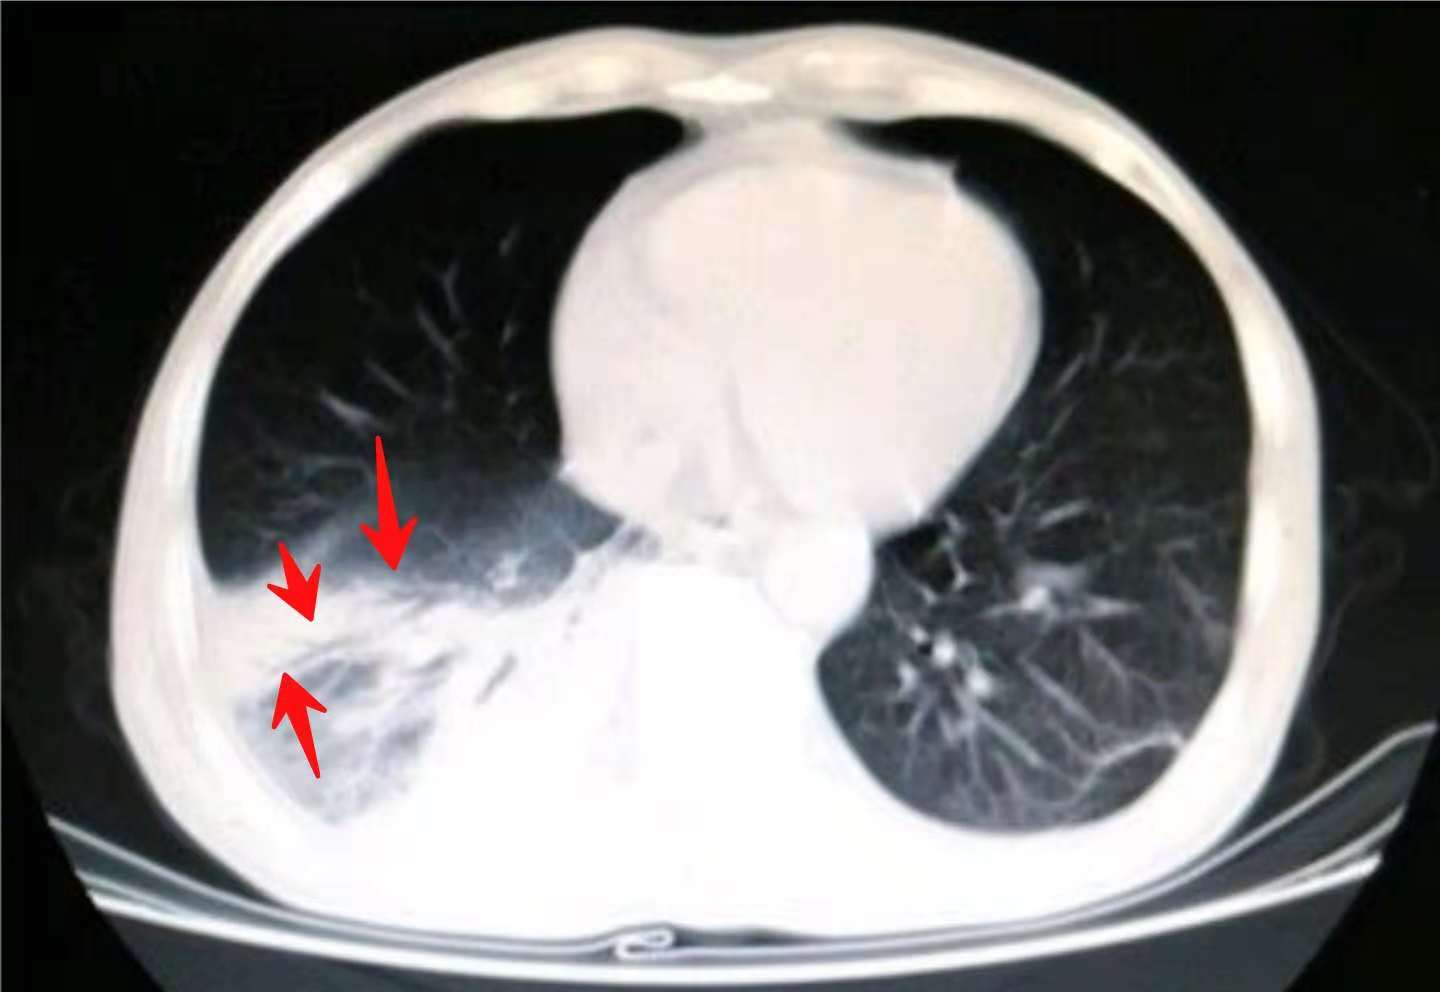

上图这位老人,在72岁的时候发现左侧早期肺癌,觉得年纪大了,没有选择手术也没有采用其他任何治疗。

11年后,老人83岁的时候最后一次来复查,肿瘤已经进展到晚期:

肺腺癌早期大多进展缓慢,甚至可达数年,仅表现为肺内高危结节(这也是我们呼吁重视胸部体检的原因,通过体检做到早期发现及时处理,解除风险)。